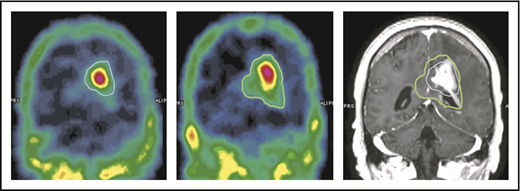

BBB permeability assessed by SPECT

The capability of NGR-hTNF to increase vascular permeability in tumor and perilesional areas was confirmed by results of SPECT studies. Quantitative analysis showed an increase in the extent of the 99mTc-DTPA–positive region(s) in all the investigated cases (an example is given in Figure 5). The median volume of ≥30% 99mTc-DTPA uptake (volume of interest) measured before and after the infusion of NGR-hTNF/R-CHOP was 26 cm3 (range, 5-67 cm3) and 40 cm3 (range, 10-92 cm3), respectively (P = .028). There was a median volume increase of 45%, with a range of 14% to 87%.

An example of increase of 99mTc-DTPA uptake after the infusion of NGR-hTNF followed by R-CHOP at the third course of treatment. The volume of ≥30% 99mTc-DTPA uptake is contoured in 2 SPECT studies performed before (left image, blue line) and after (middle image, green line) administration of NGR-hTNF and R-CHOP. Comparison of contoured volumes are represented in the gadolinium-enhanced T1-weighted MRI showing the tumor (right image). The volume of interest before and after NGR-hTNF/R-CHOP delivery was 22 cm3 and 40 cm3, respectively.